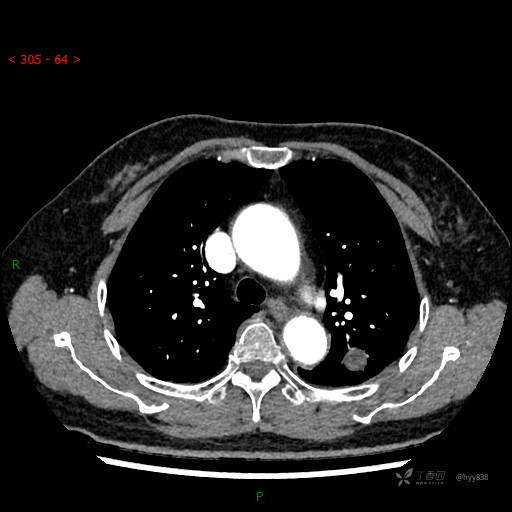

静脉期

各期CT值:28hu、58hu、69hu